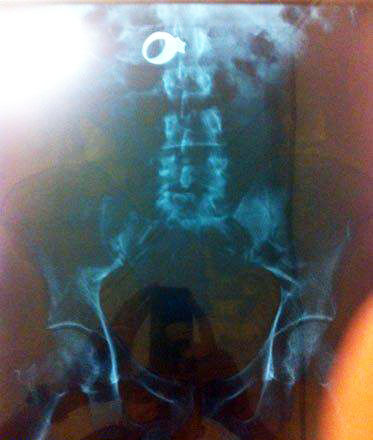

瓶は変態系統のお遊びの結果だろうな

お尻は日本でもたまーに救急に来るで

肛門に異物はよくあるらしい。やり過ぎると地主になってしまうので程ほどにね。

尻に異物が入る時はだいたい「転んだ拍子に」って言うけど医療関係者はそんな与太話は誰も信じてないだろうね。